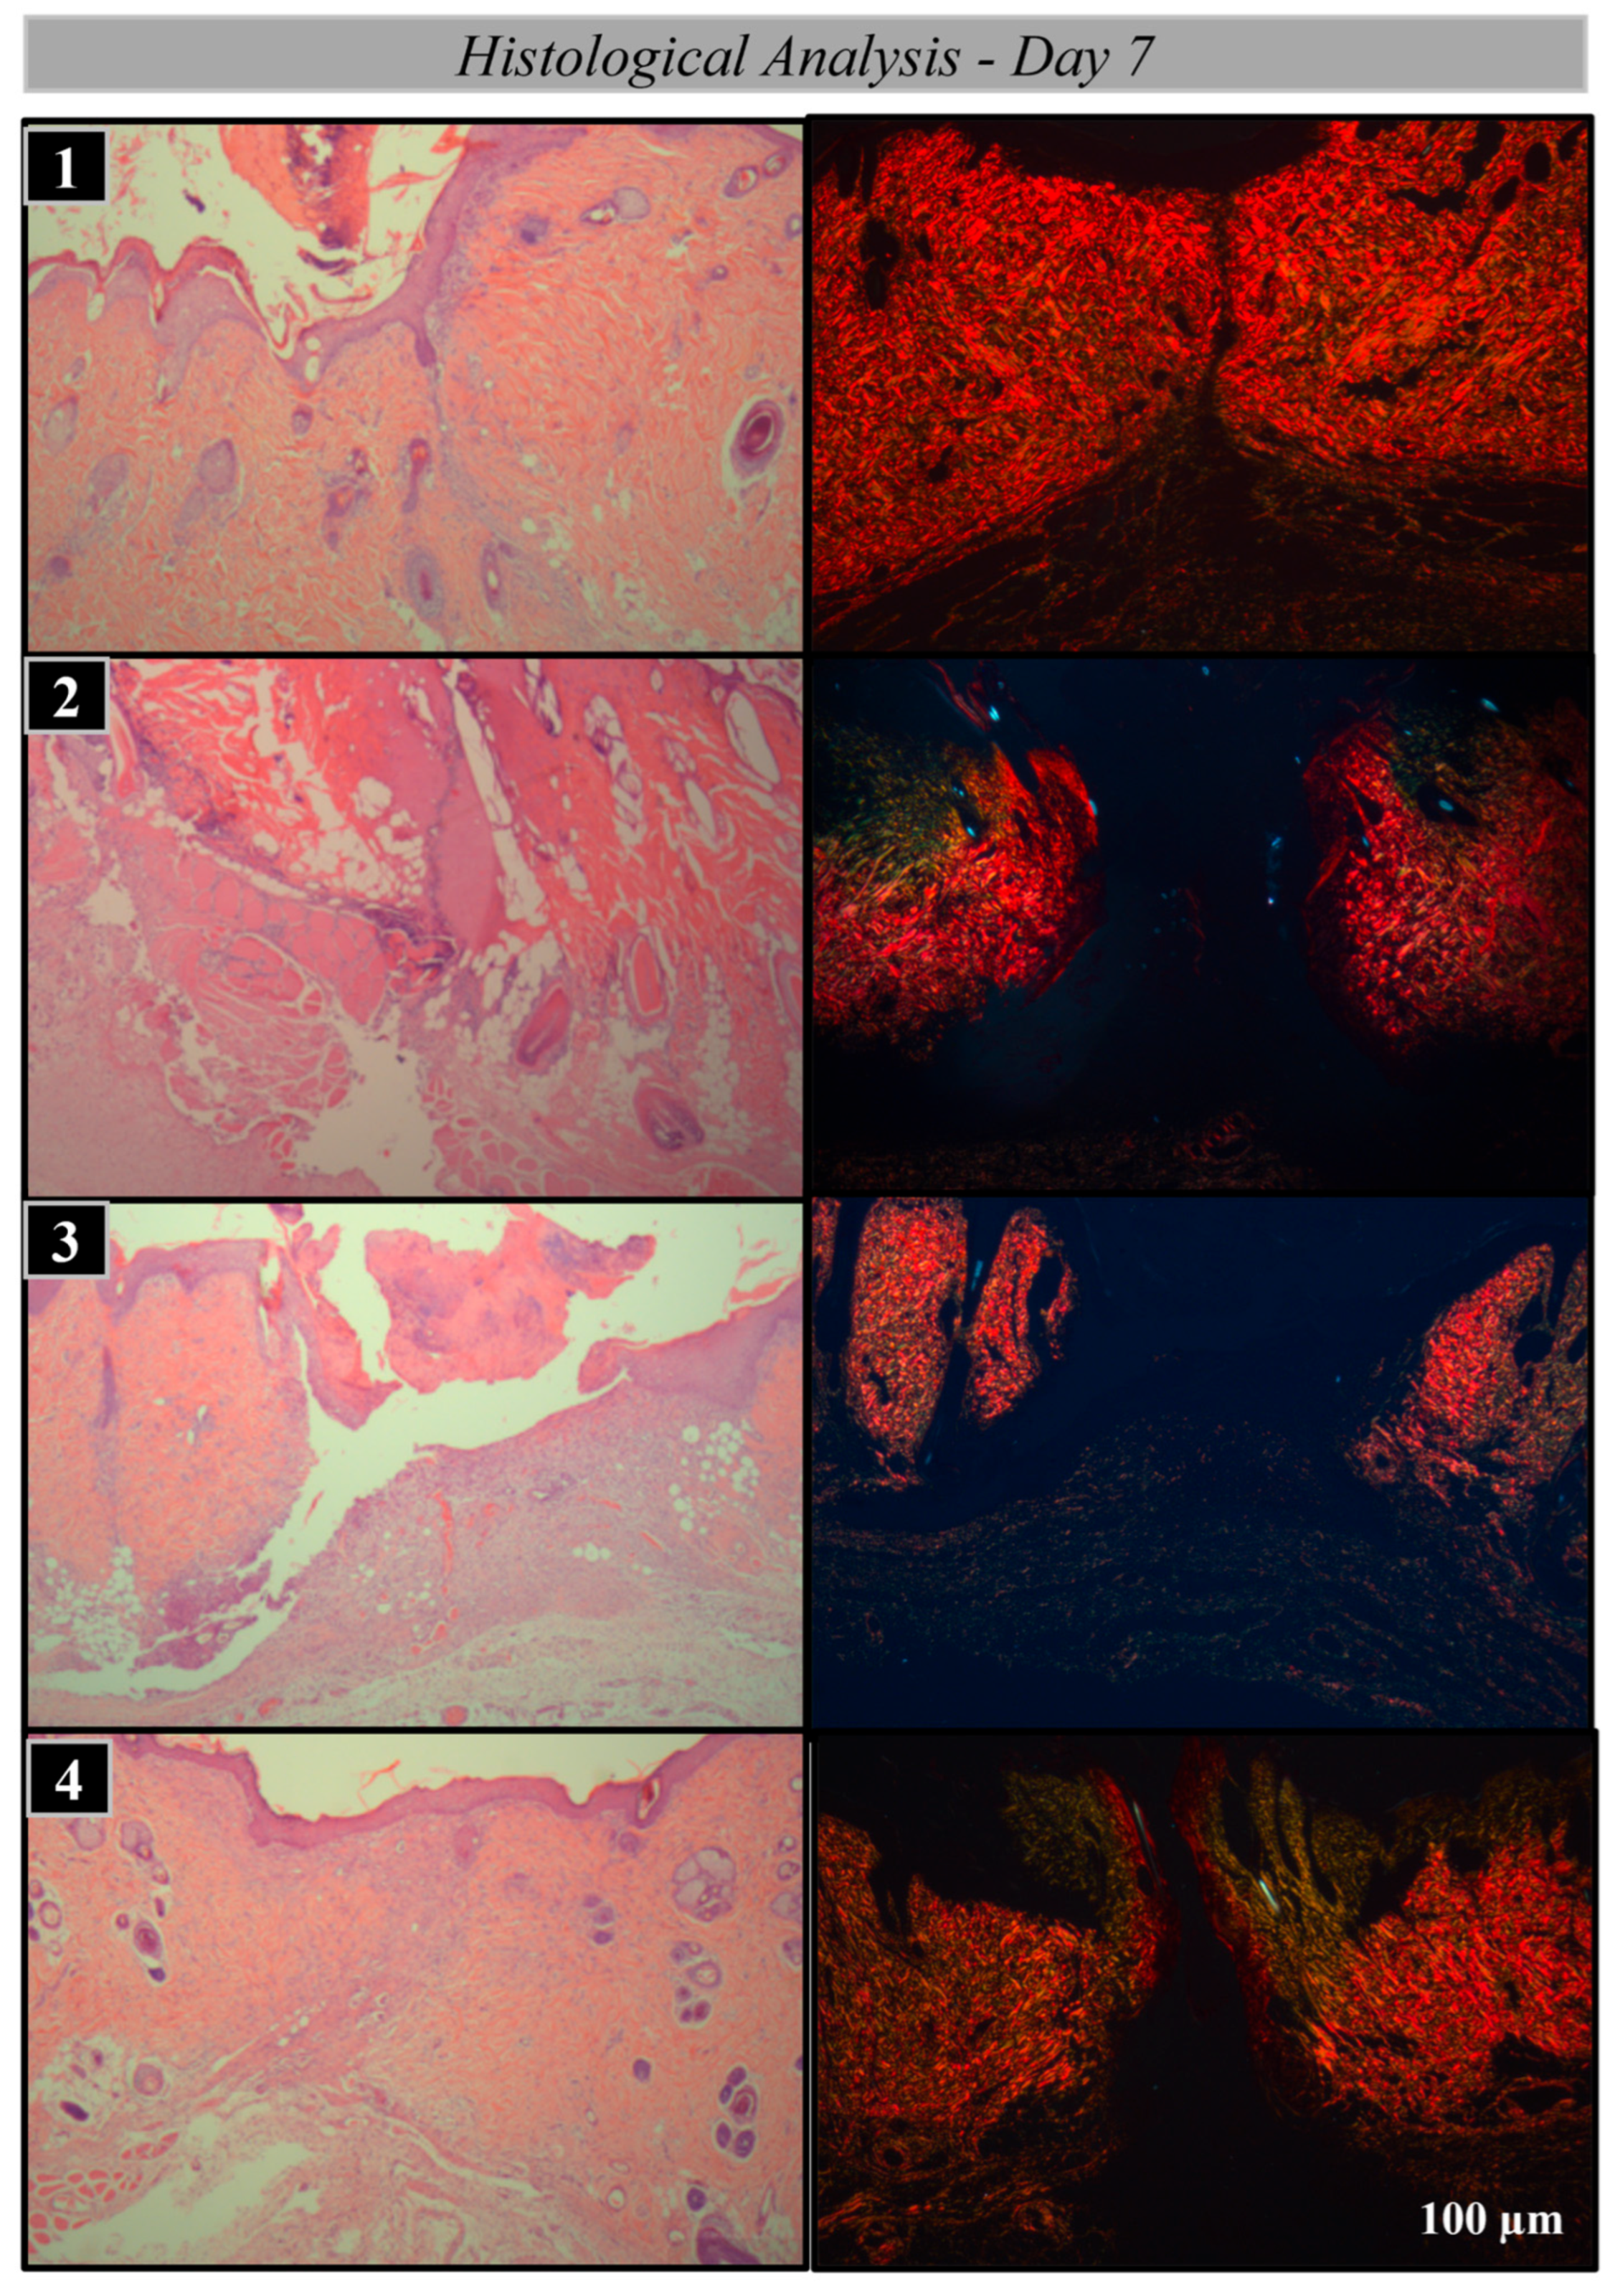

Histological and Histomorphometric Analysis